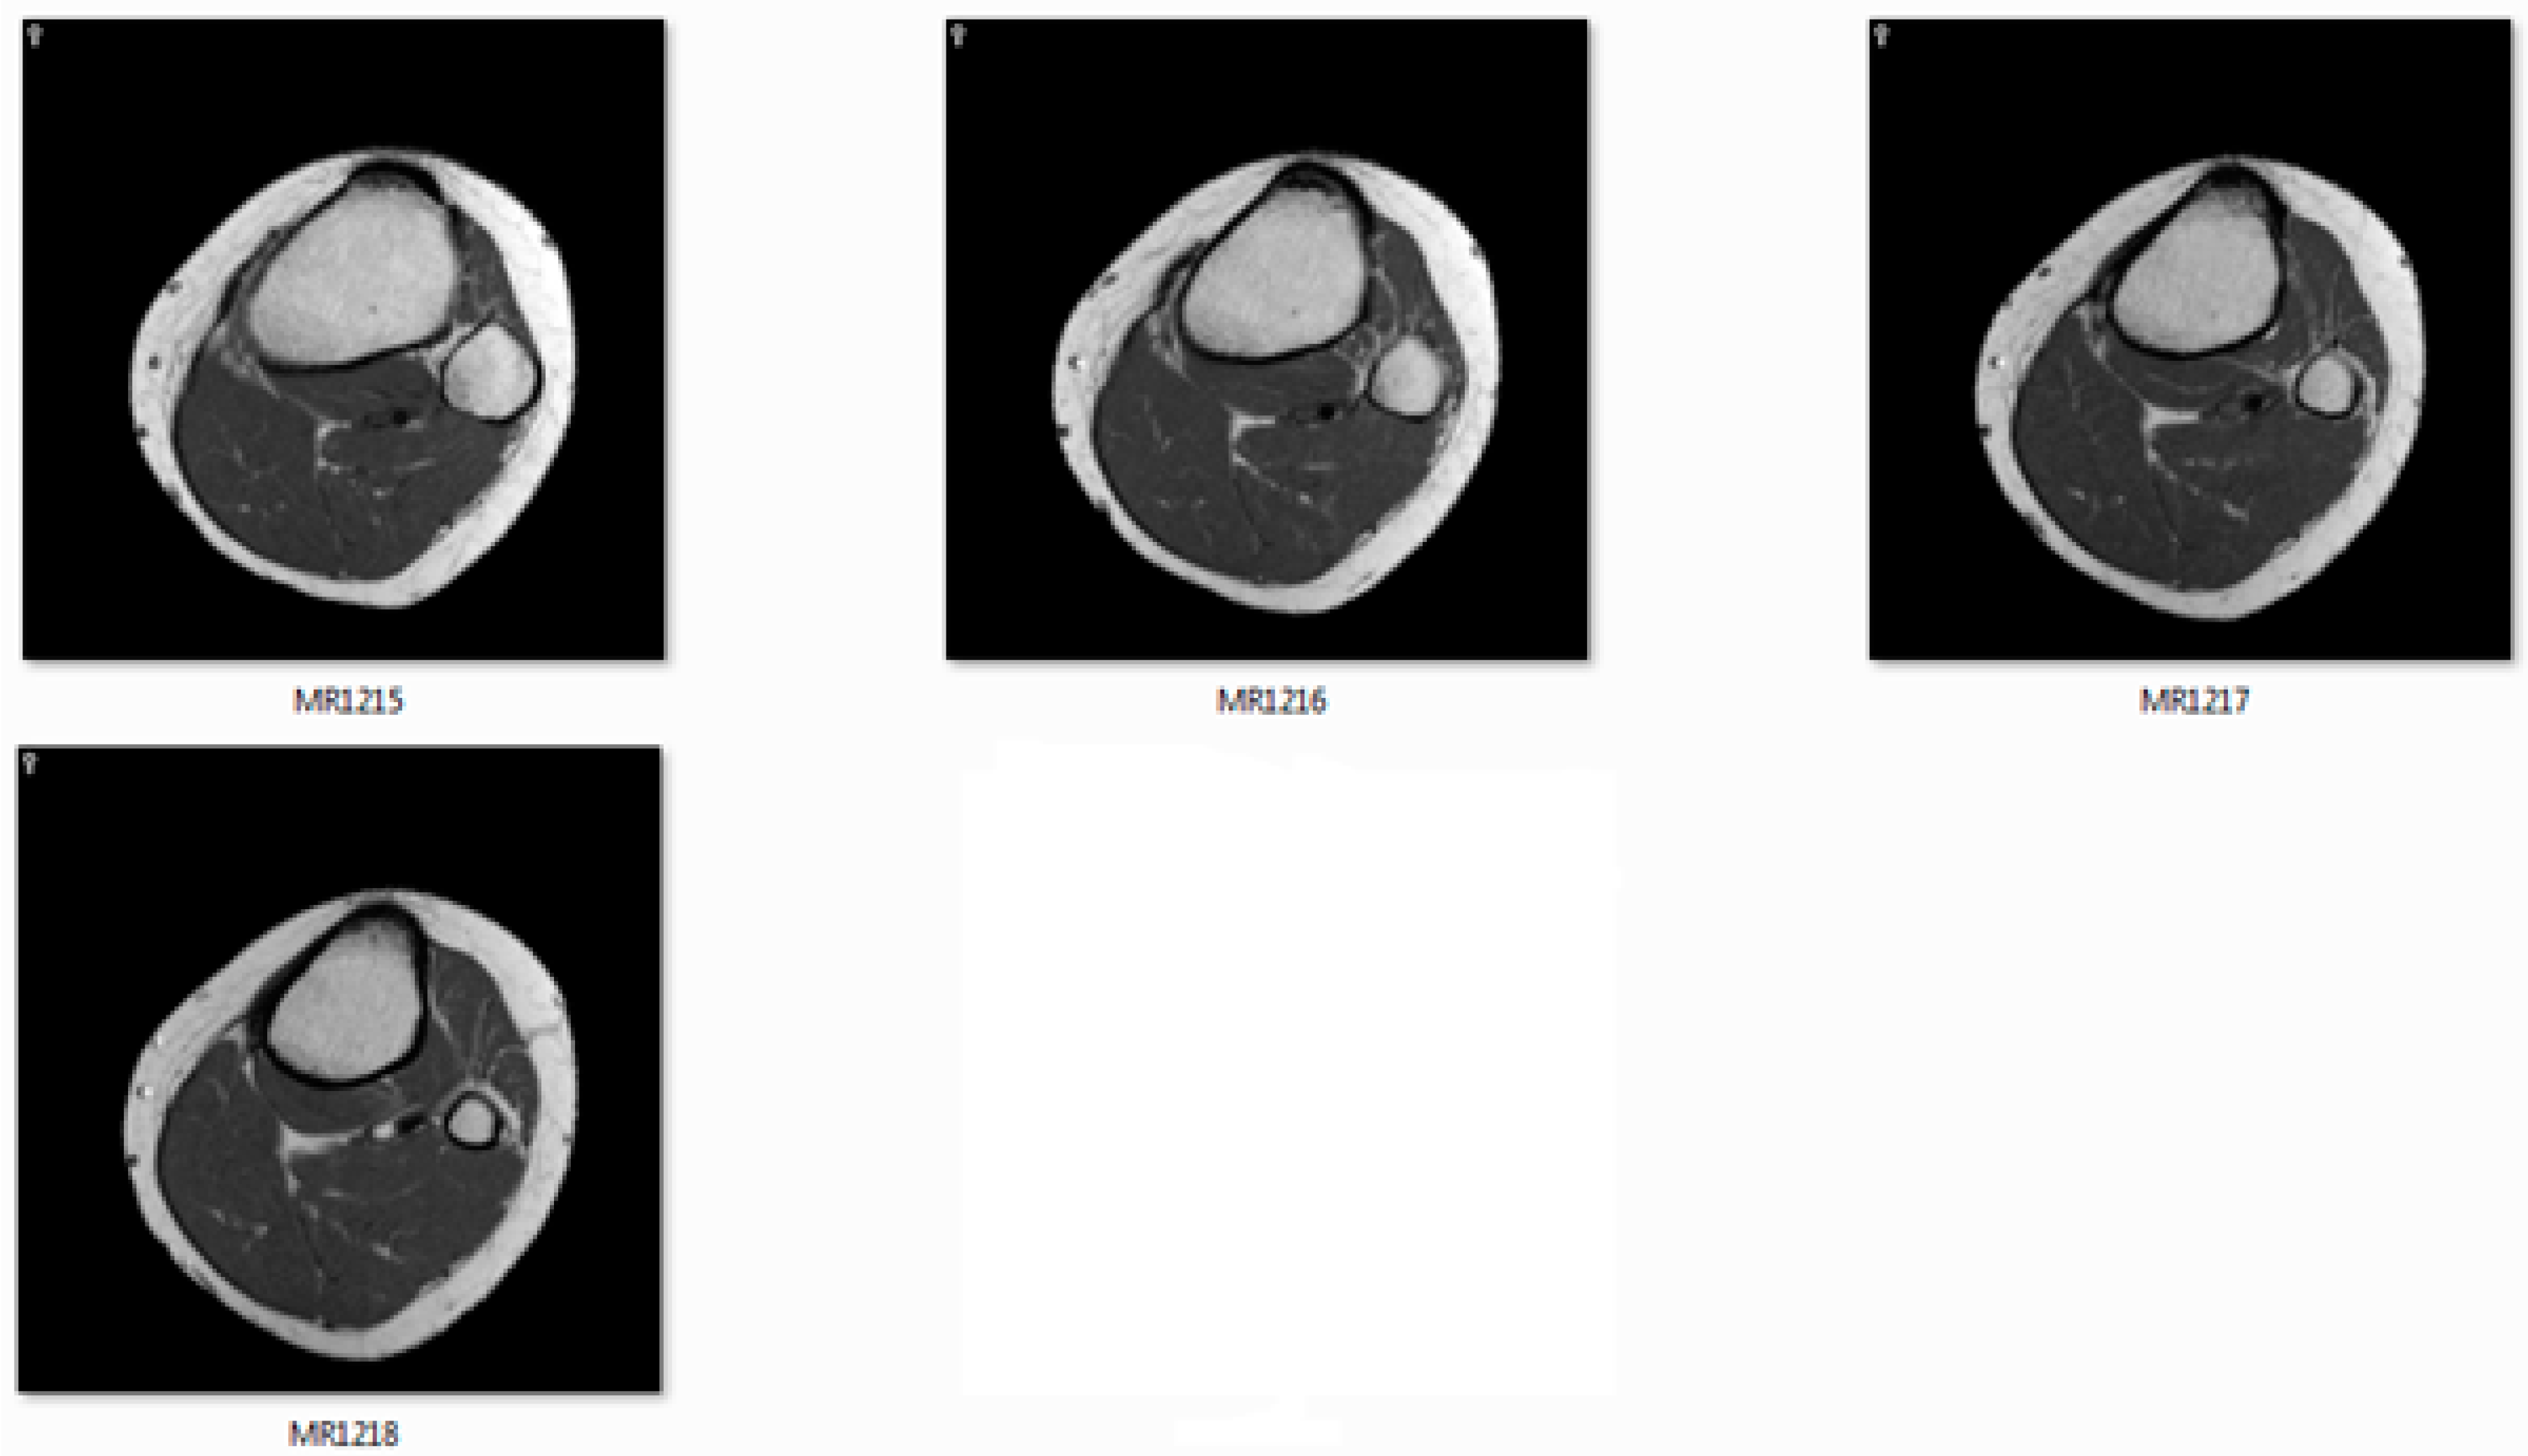

The CT/MRI of 32/64/128 slides must be provided to use as input images. Figure 11 shows the MRI slides of human knee.

Figure 11.

The image slides used as input data.